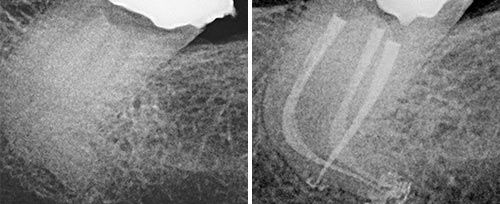

Endodontic Treatment

Courtesy of: Giovanni Olivi, MD, DDS

Laser source: Er:YAG (2940 nm)